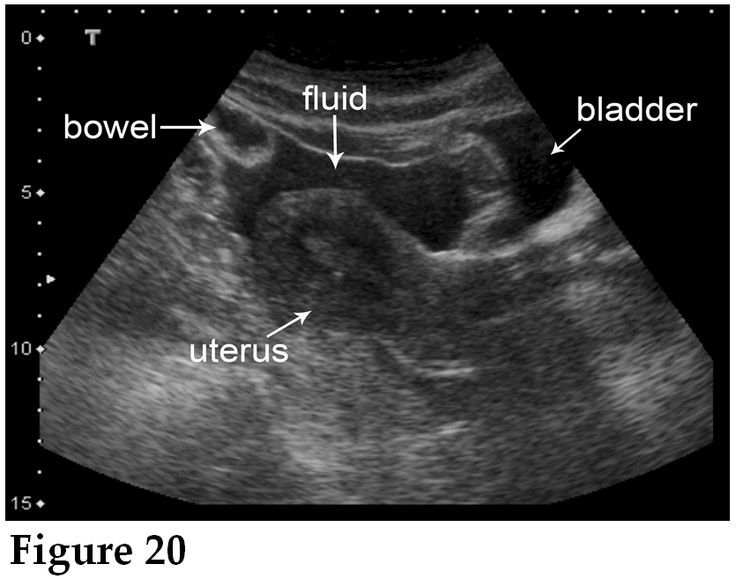

[T or F] Posterior Cul-De-Sac fluid accumulation in a pregnant woman is an abnormal finding

FALSE

(this is a normal finding for preggos along with corpus luteum ovarian cyst UNLESS IT’S IN THE SETTING OF ECTOPIC. THEN IT MEANS HEMOPERITONEUM)